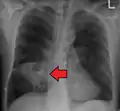

Lung abscesses are often on one side and single involving posterior segments of the upper lobes and the apical segments of the lower lobes as these areas are gravity dependent when lying down. Presence of air-fluid levels implies rupture into the bronchial tree or rarely growth of gas forming organism.

Pulmonary abscess on CXR